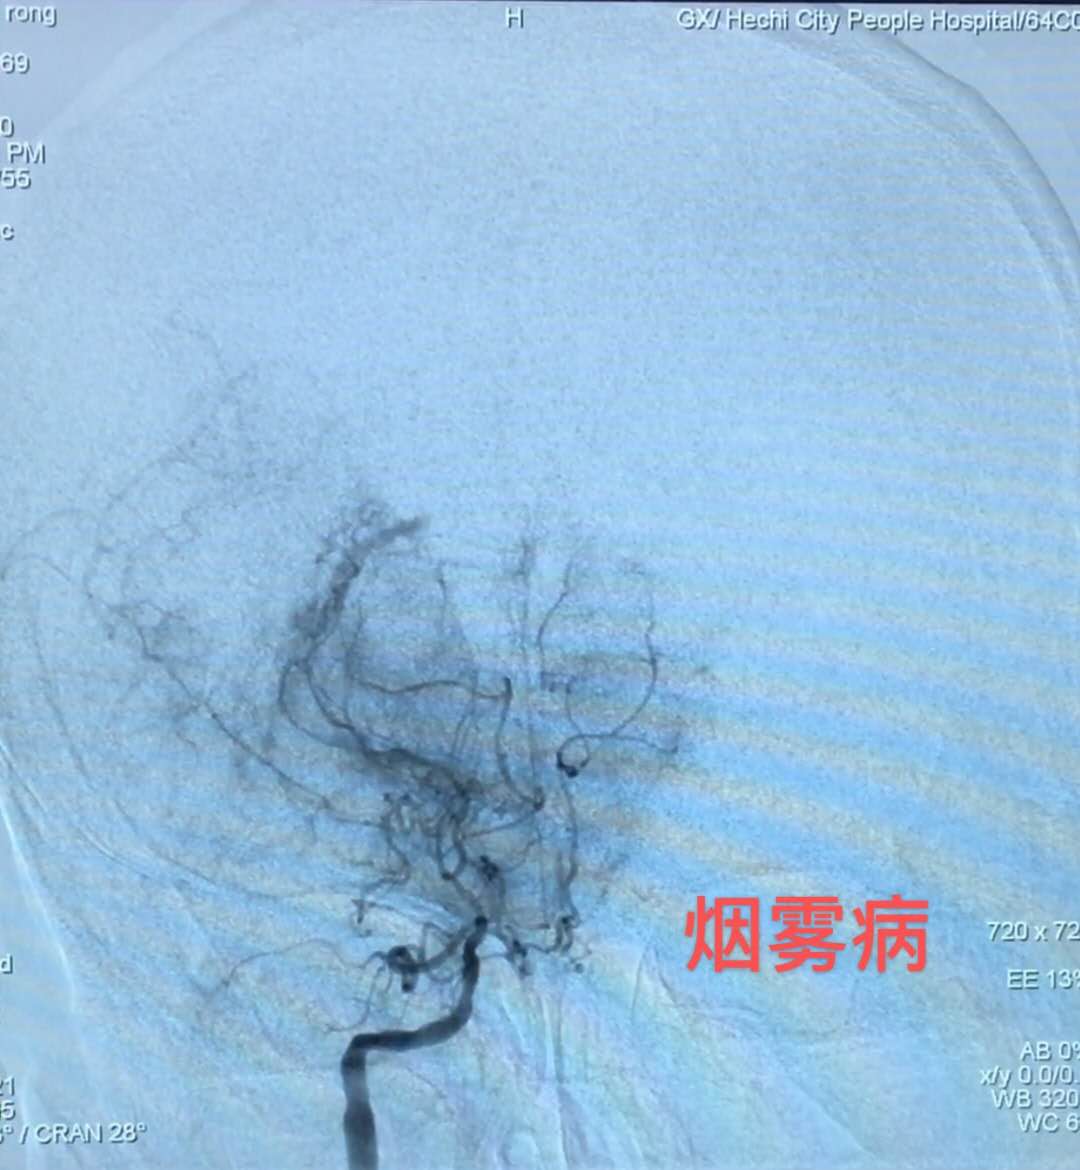

据了解,51岁的候先生因“突发意识障碍”被工友送至我院急诊科,急诊CT提示蛛网膜下腔出血,收治神经外科后立刻进行CTA检查,确诊为基底动脉顶端动脉瘤破裂出血。这是一种致残率和死亡率很高的病变,如果不及时处理,随时都有可能发生病情恶化甚至死亡。神经外科医疗团队当即组织制定详细的手术治疗方案,在与家属充分沟通后,在最短的时间内为侯叔叔进行了全脑血管造影术、底动脉顶端动脉瘤电解脱弹簧圈介入栓塞术。术中造影显示侯叔叔的颅底出现云状异常,可见基底动脉顶端一大小约6.5mm×5.8mm×2.8mm的囊性动脉瘤,且伴有“烟雾病”。手术医生要在变形变细、形似云雾缭绕、错综交织的血管内找到动脉瘤并摘除,手术难度非常大……最终经过3个半小时的努力,手术顺利完成。术后,在经过4次腰椎穿刺术等后续相关辅助治疗后,患者恢复清醒,并无神经系统相关并发症,终于转危为安,现已康复出院。

烟雾病